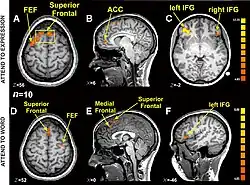

Cognitive and affective "paths": brain imaging data

Different brain structures involved in the recognition of a word, and in the recognition of an emotional expression (functional MRI).[48]

These fMRI images are from a study showing parts of the brain that respond to seeing houses and other parts to seeing faces. The 'r' values are correlations, with higher positive or negative values indicating a better match.[49]

Research using functional magnetic resonance imaging of the brain suggests that cognitive and affective-expressive forms of communication and self-reflection have distinct neural bases.[50] Clinical findings have long suggested that verbalizations are often very incoherent when the individual is trying to put into words something deeply emotional.[51] Identification of words naming emotions (happy, neutral, sad) was found to be faster than identification of corresponding facial expressions. Recognition of face expressions was more difficult to suppress in favor of the recognition of words than vice versa, the two conditions presenting different patterns of brain activation. These experimental results suggest that reading and recognition of face expressions are stimulus-dependent and perhaps hierarchical behaviors, hence recruiting distinct regions of the medial prefrontal cortex.[48]

Research indicates that the representations of faces and objects in ventral temporal cortex are widely distributed and overlapping, face stimuli eliciting response patterns distinct from those elicited by object stimuli.[49]